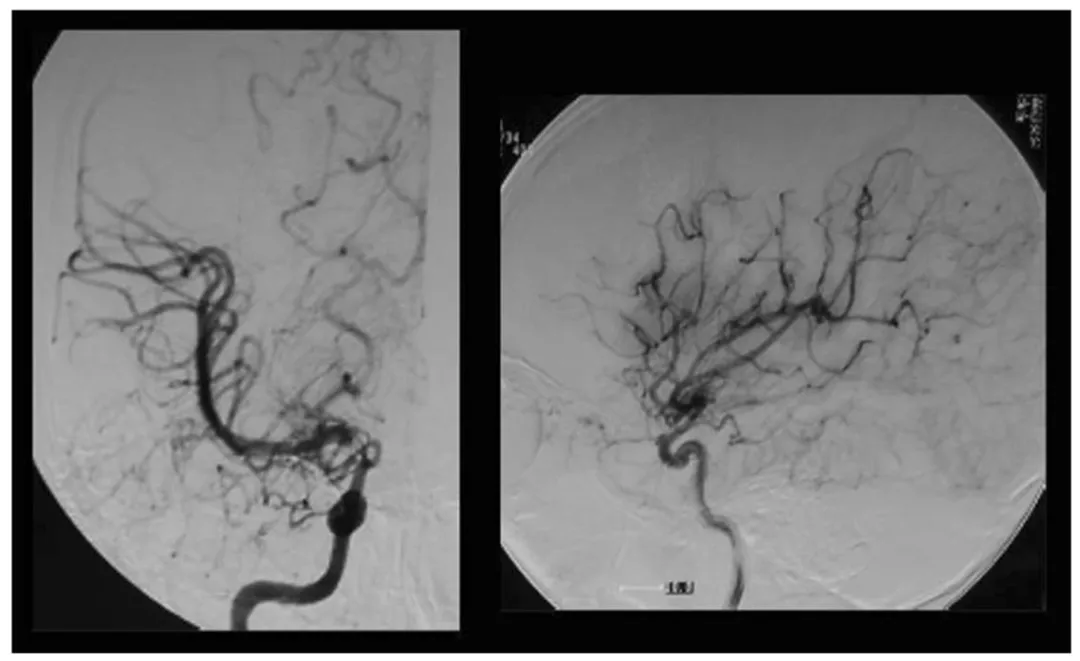

图1,术前右颈动脉血管造影显示IC末端顶部烟雾血管发育,左:前后视图,右:侧视图

血管造影显示:她的右侧颈内动脉末端已经狭窄,大脑里长出了细小的“烟雾状血管”,病情处于铃木分期II期(Suzuki分期,是早期),甚至快过渡到III期;左侧血管暂时正常。(图1)